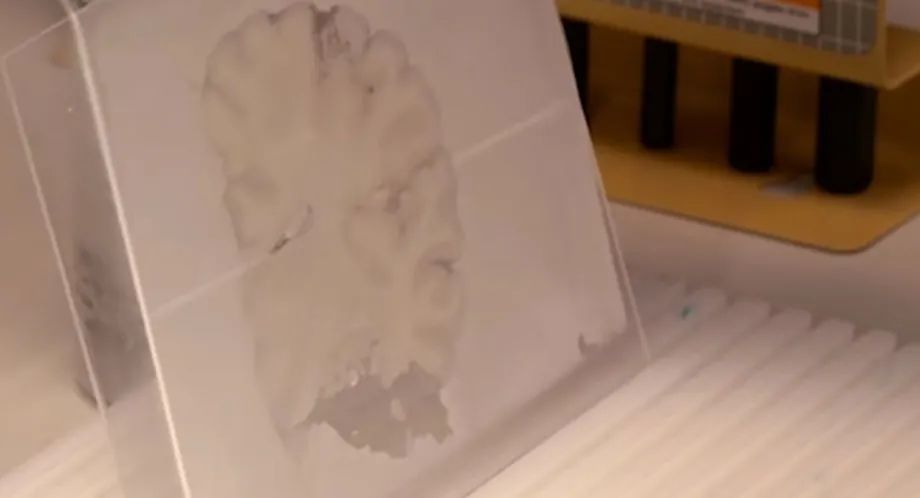

染色